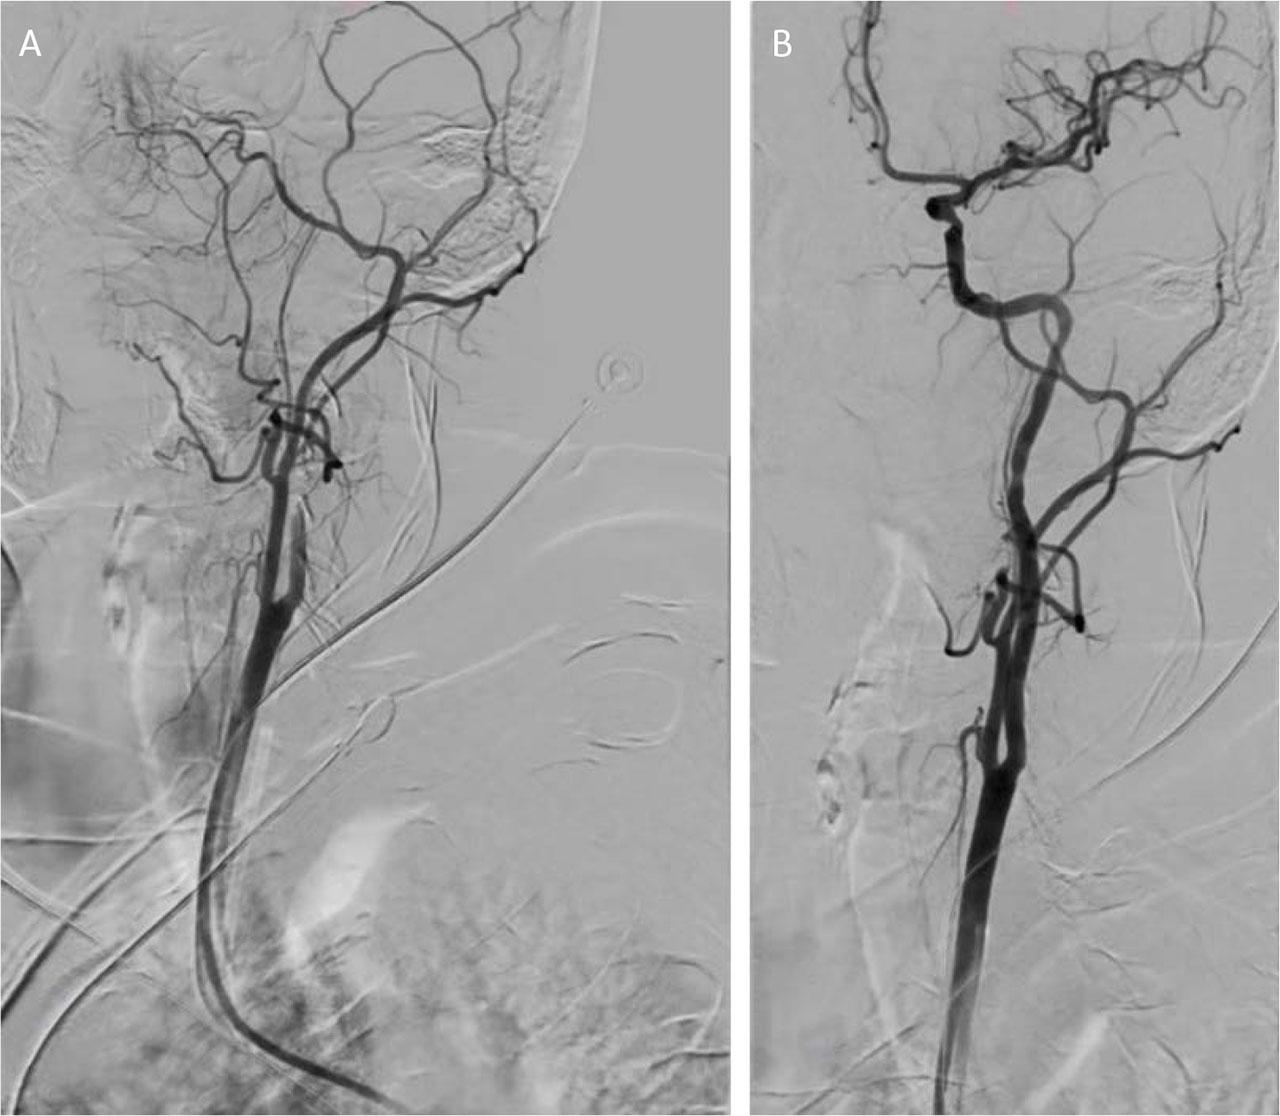

On the fourth day of hospitalization, the patient experienced sudden neurological deterioration. Emergency echocardiography indicated embolization of the thrombus from the left ventricular apex. Cerebral CT angiography revealed an acute thrombotic occlusion of the left internal carotid artery. In accordance with the European Stroke Organization guidelines for patients with acute ischemic stroke caused by large vessel occlusion within 6 hours of symptom onset, emergency thrombectomy was performed, resulting in successful extraction of the thrombotic material (Figure 4 A,B). A native CT scan performed 24 hours post-intervention showed no evidence of cerebral ischemic lesions (Figure 5). Echocardiography confirmed the absence of the apical thrombus in the left ventricle.

Emergency thrombectomy procedure